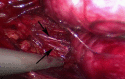

Presentation of case: We describe a case of a 44 year old patient with a laparoscopic approach for the removal of a retrorectal tumor and emphasize on the preoperative diagnostics and the intraoperative, minimal invasive approach.

Discussion: Especially because these tumors are rare and often an incidental finding in gynecologic surgery, it is important to know the various differential diagnoses and its consequences with the laparoscopic approach.

Conclusion: We suggest the laparoscopic approach in cases of retroperitoneal cysts of unknown origin is ideal also because anatomic structures, mostly nerves, can be easily spared.